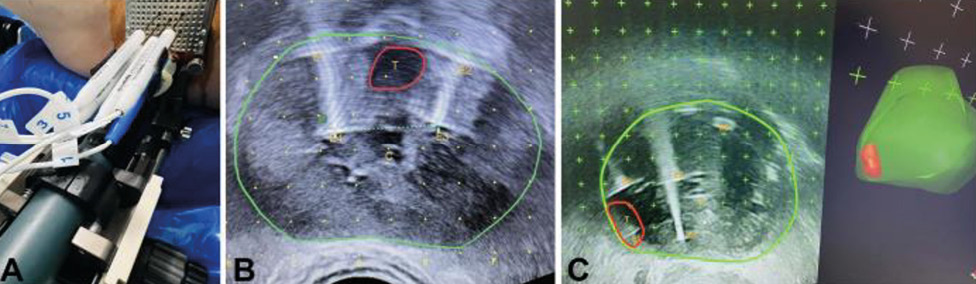

У групі первинного лікування середній рівень простато­специфічного антигену (ПСА) через 6 міс після лікування становив 3,4 нг/мл (0,8–16,3) порівняно із середнім показником до лікування 5,6 нг/мл (1,5–25), що свідчить про зниження на 39%. При контрольній мультипараметричній МРТ (мпМРТ) (рис. 2) через 6 міс після лікування у 84% пацієнтів (25/38) не було ознак хвороби при порівнянні результатів мпМРТ (Prostate Imaging Reporting and Data System — PI-RADS) = 2, тоді як у 12% виявлено нові підозрілі вогнища ураження поза межами зони абляції (PI-RADS >3), а у 4% зберігалося ураження в межах зони абляції. Контроль промежинної біопсії проведено через 1 рік після лікування (раніше, якщо на МРТ були ознаки залишкової хвороби) 13 пацієнтам. У 69% не виявлено ознак захворювання, у 31% (N-4) діагностовано клінічно значущий рак передміхурової залози за межами зон абляції (ISUP >2), клінічно значущих уражень у межах зони абляції не зафіксовано у жодного хворого. Загалом впродовж 1 року після лікування 2 пацієнти пройшли повторну НОЕ, а 1 — радикальну простатектомію, отже, 97% пацієнтів перебували під активним спостереженням. Через 2 роки із 13 пацієнтів двом проведено радикальну простатектомію, 4 пройшли повторну НОЕ і загалом 84% (11/13) залишалися під АС.

Рис. 2. МРТ передміхурової залози до та після лікування за допомогою НОЕ. Пацієнт віком 75 років із нещодавно діагностованою злоякісною пухлиною, ISUP 2, у периферійній зоні (PZ) справа, що охоплює верхівку та середню частину цієї залози. (a) МРТ до лікування. У PZ на Т2-WI видно низьку інтенсивність сигналу (стрілка) (a1), що відповідає обмеженому низькому сигналу ADC (a2) та високому сигналу на DWI (a3). Це корелювало з артеріальним підсиленням (a4). (b) МРТ через 6 міс після лікування. Відмічається підвищення низького сигналу на Т2-WI у зоні лікування, що є наслідком очікуваної атрофії (b1), з неоднорідним сигналом на ADC (b2) та відсутністю обмеження на DWI (b3). Крім того, підсилення більше не виявляється (b4) [цит. за 2]

Примітки: ISUP — ступінь агресивності раку передміхурової залози за класифікацією Міжнародного товариства урологічної патології (International Society of Urological Pathology); Т2-WI — Т2-зважені зображення; DWI — дифузійно-зважені зображення.